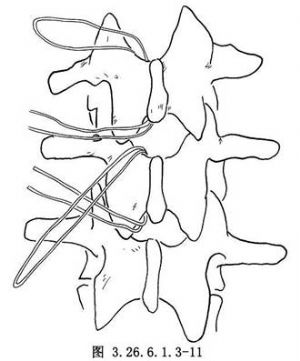

取30cm長的醫用鋼絲(直徑1mm),將其對摺,形成雙股,將摺疊鈍端彎成半徑3cm的半圓弧狀。將鈍端插入黃韌帶窗內用雙手使鋼絲貼緊椎板下面通過椎板,鋼絲鈍端由上節椎板的黃韌帶窗露出後,用針持夾夾緊鋼絲鈍端,並提起保持鋼絲張力,將鋼絲由椎板下抽出至椎板上,上下端的鋼絲長度相等爲止,將上下兩段鋼絲交叉於椎板上,以防止鋼絲向椎管內移動壓迫硬膜(圖3.26.6.1.3-11)。